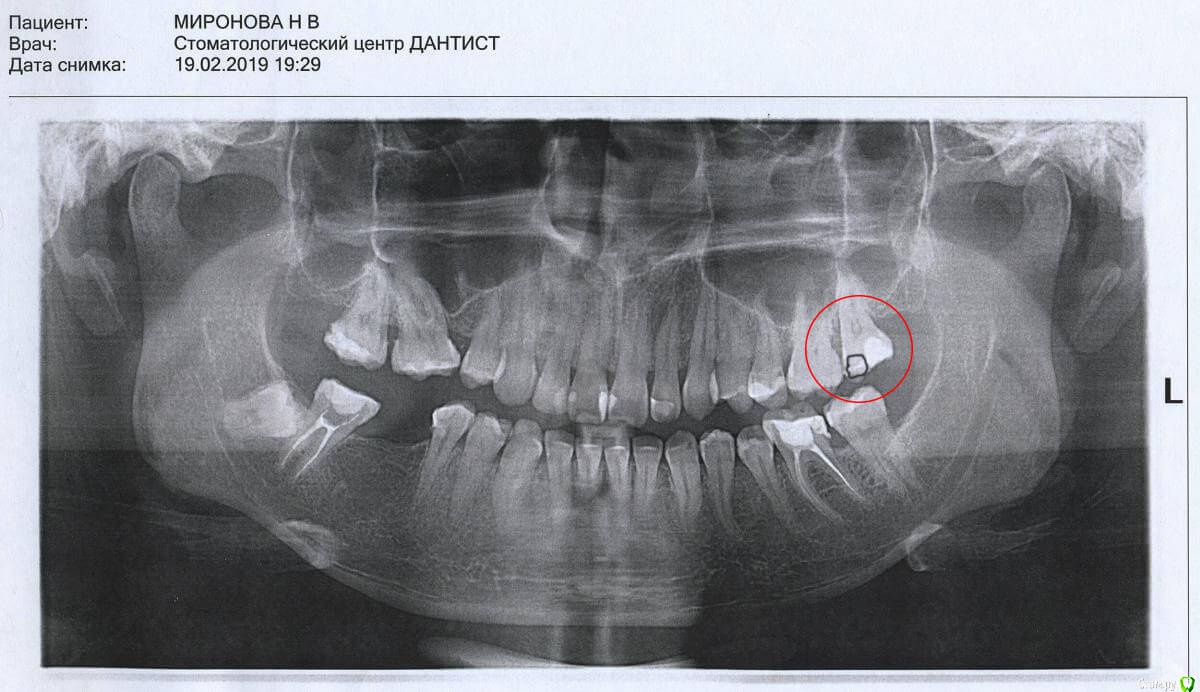

nataganka Опубликовано 9 декабря, 2019 Автор Поделиться Опубликовано 9 декабря, 2019 Нет, ну я точно перешла дорогу какой-то зубной феечке, у меня уже смех истерический))))) ладно бы гигиену не соблюдала, но нет ведь, и нитью пользуюсь после еды, и ирригатором пользуюсь и щетка электрическая))))))) видимо и впрямь наследственность такая штука коварная. В общем, не успела я заняться удалением ретинированного 48-го зуба... так как теперь финансы потекли в зуб 27. И полугода не прошло. У меня там была пятилетней давности пломба, которая не вызывала ни у кого вопросов собственно на осмотрах и лечении зубов все начало этого года. В ноябре откололся кусочек пломбы, при том ела обычную пищу, не твердую. Под ней внутри зуба оказалась кариозная полость и довольно таки обширная, глазом пока пломба не откололась ее не было видно ни одному врачу, коих я посетила за этот год множество (( Так вот теперь предстоит лечение, либо обойдется пломбой, либо снова депульпация и коронка с вкладкой. По снимку врачи сказали, что на грани, все станет ясно на лечении. Как мне снять карму со своих зубов, чтобы денег хватало на жизнь и одежду, а не относила все финансы в стоматологию? Вопрос походу риторический))))))))))А теперь вопрос фактический, если все-таки будут депульпировать, то можно ли потом это все закрыть керамической реставрацией, а не вкладку+коронку? Сфоткать во рту у меня не получится, по причине расположения зуба. Снимок с предыдущей страницы. Зуб и кариозная полость отмечена Ссылка на комментарий